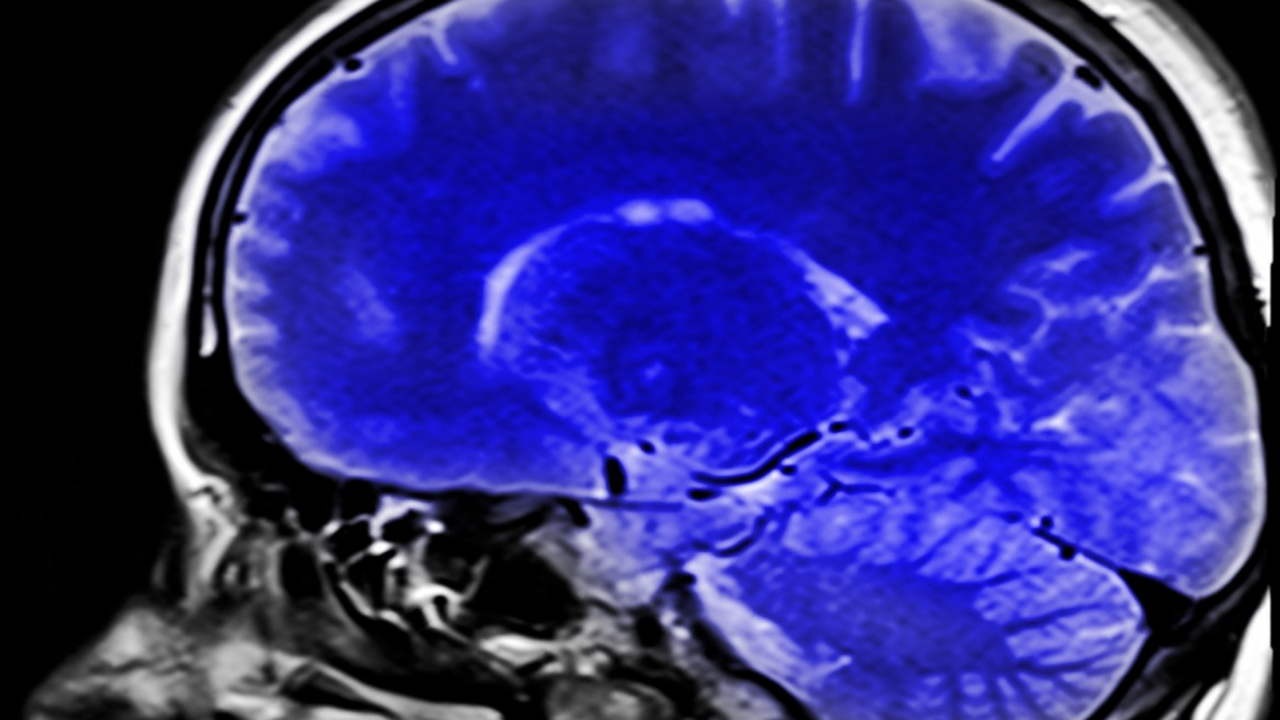

Исследование, опубликованное 16 января в научном журнале Alzheimer’s & Dementia, выявило ключевые генетические особенности так называемых «супердолгожителей» — людей старше 80 лет, чьи когнитивные функции соответствуют уровню людей на 20–30 лет моложе. Работу провели учёные из Медицинского центра Университета Вандербильта, проанализировав данные 18 080 участников.

Главным выводом стало то, что «супердолгожители» значительно реже являются носителями варианта гена APOE-ε4 — самого сильного из известных генетических факторов риска болезни Альцгеймера. По сравнению с более молодыми пожилыми людьми эта группа на 68% реже имела данный вариант гена. Даже в сравнении со сверстниками с обычным когнитивным старением APOE-ε4 у них встречался на 19% реже.

Впервые исследователям также удалось показать, что у «супердолгожителей» чаще обнаруживается защитный вариант гена APOE-ε2. По сравнению с обычными 80-летними участниками исследования, представители этой группы на 28% чаще были его носителями. Этот вариант гена ранее связывали со сниженным риском развития болезни Альцгеймера и других форм деменции.

По словам ведущего автора исследования Лесли Гейнор, полученные данные позволяют рассматривать фенотип «супердолгожителя» как особую категорию пожилых людей с пониженным генетическим риском нейродегенеративных заболеваний. Учёные считают, что изучение этой группы может помочь лучше понять механизмы устойчивости мозга к возрастным изменениям.

Исследователи надеются, что дальнейшая работа в этом направлении позволит выявить биологические факторы, способствующие сохранению памяти и мышления в глубокой старости. В перспективе такие открытия могут стать основой для разработки новых подходов к профилактике и лечению болезни Альцгеймера и других нейродегенеративных заболеваний, пишет источник.